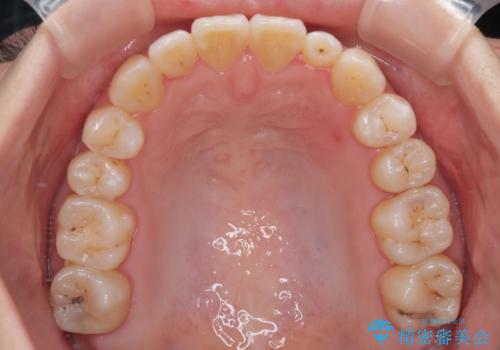

- 矯正装置

- 審美装置

- 1年6ヶ月

診査の結果、上下顎ともに叢生が認められましたが、ワイヤー矯正・マウスピース矯正のいずれでも対応可能な症例でした。

という患者様のご希望を踏まえ、プラスチックブラケット+コーティングワイヤーを用いたワイヤー矯正を選択しました。